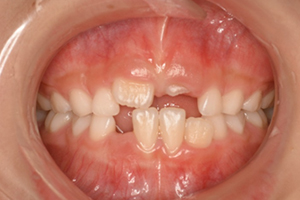

永久歯が出てくるスペースが不足

治療内容・期間 左が5歳の時の、右が7歳の時です。どちらも矯正治療前の写真です。5歳の時(左)、下の前歯2本(緑の矢印)は、左右ともにAとBの癒合歯で、2つで1つの歯になっていましたので、本数が2本不足でした。 時点でX線撮影を行ったところ、埋まっている永久歯の数は正常でした。乳歯より多い数の永久歯が出てくるためにス...